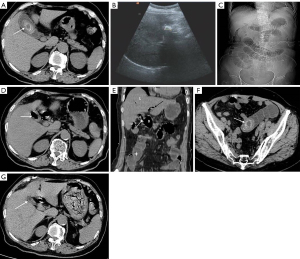

The patient reported a 5-day history of abdominal pain with distension and diarrhea, along with a 1-day history of body pain, high fever (up to 39.6 ℃), and chills. The US showed liver cirrhosis, splenomegaly, and the presence of innumerable gallstones. The blood test results were as follows: leukocyte count, 10.66×109/L; neutrophil, 90.3%; total bilirubin, 45.20 µmol/ L; direct bilirubin, 30.90 µmol/L; ALT, 45 U/L; and AST, 64 U/L. In addition, the patient had a medical history of hypertension, diabetes, chronic schistosomiasis, hepatopathy, and cholelithiasis. The PE showed mild abdominal tenderness to palpation, the presence of abdominal wall varicose veins, and a positive Murphy sign. No rebound pain or moving sounds were detected. Abdominal CT revealed a lesion of hypodensity in the left lobe of the liver with a few air bubbles inside the lesion. Some peritoneal effusions were seen surrounding the liver, suggesting the presence of a hepatic abscess (Figure 2A). The gallbladder was found to be significantly enlarged in size, and the wall was thickened and edematous. A few round stones (maximal diameter: up to 5.0 cm) and the presence of gas within the gallbladder were noted on CT images (Figure 2B). Notably, the border between the liver and the gallbladder was ill-defined and accompanied by the blurry fat space around it (Figure 2C). In addition, liver cirrhosis, splenomegaly, and a reticulum of varices were observed at the splenic hilum and gastroepiploic regions. Considering the patient’s underlying comorbidities, nonsurgical management was attempted. Treatment included anti-infection, liver protection, and other supportive medications. The posttreatment US found the gallbladder was not visible, and the patient felt an obvious improvement in the symptoms. The follow-up abdominal CT 2 years later revealed atrophy of the gallbladder, and no more detectable stones were observed. Other CT manifestations that were observed included liver cirrhosis, dilatation, and pneumatosis of the intrahepatic biliary duct (Figure 2D). Axial and reconstructed coronal images clearly demonstrated a fistula that formed between the gallbladder and hepatic flexure of the colon (Figure 2E,2F), which confirmed the definite diagnosis of CEF.